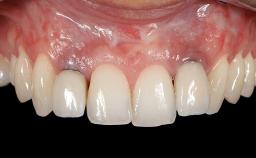

Soft-Tissue Volume Augmentation Using a Connective-Tissue Graft Harvested from the Maxillary Tuberosity

Prosthesis Type FDP